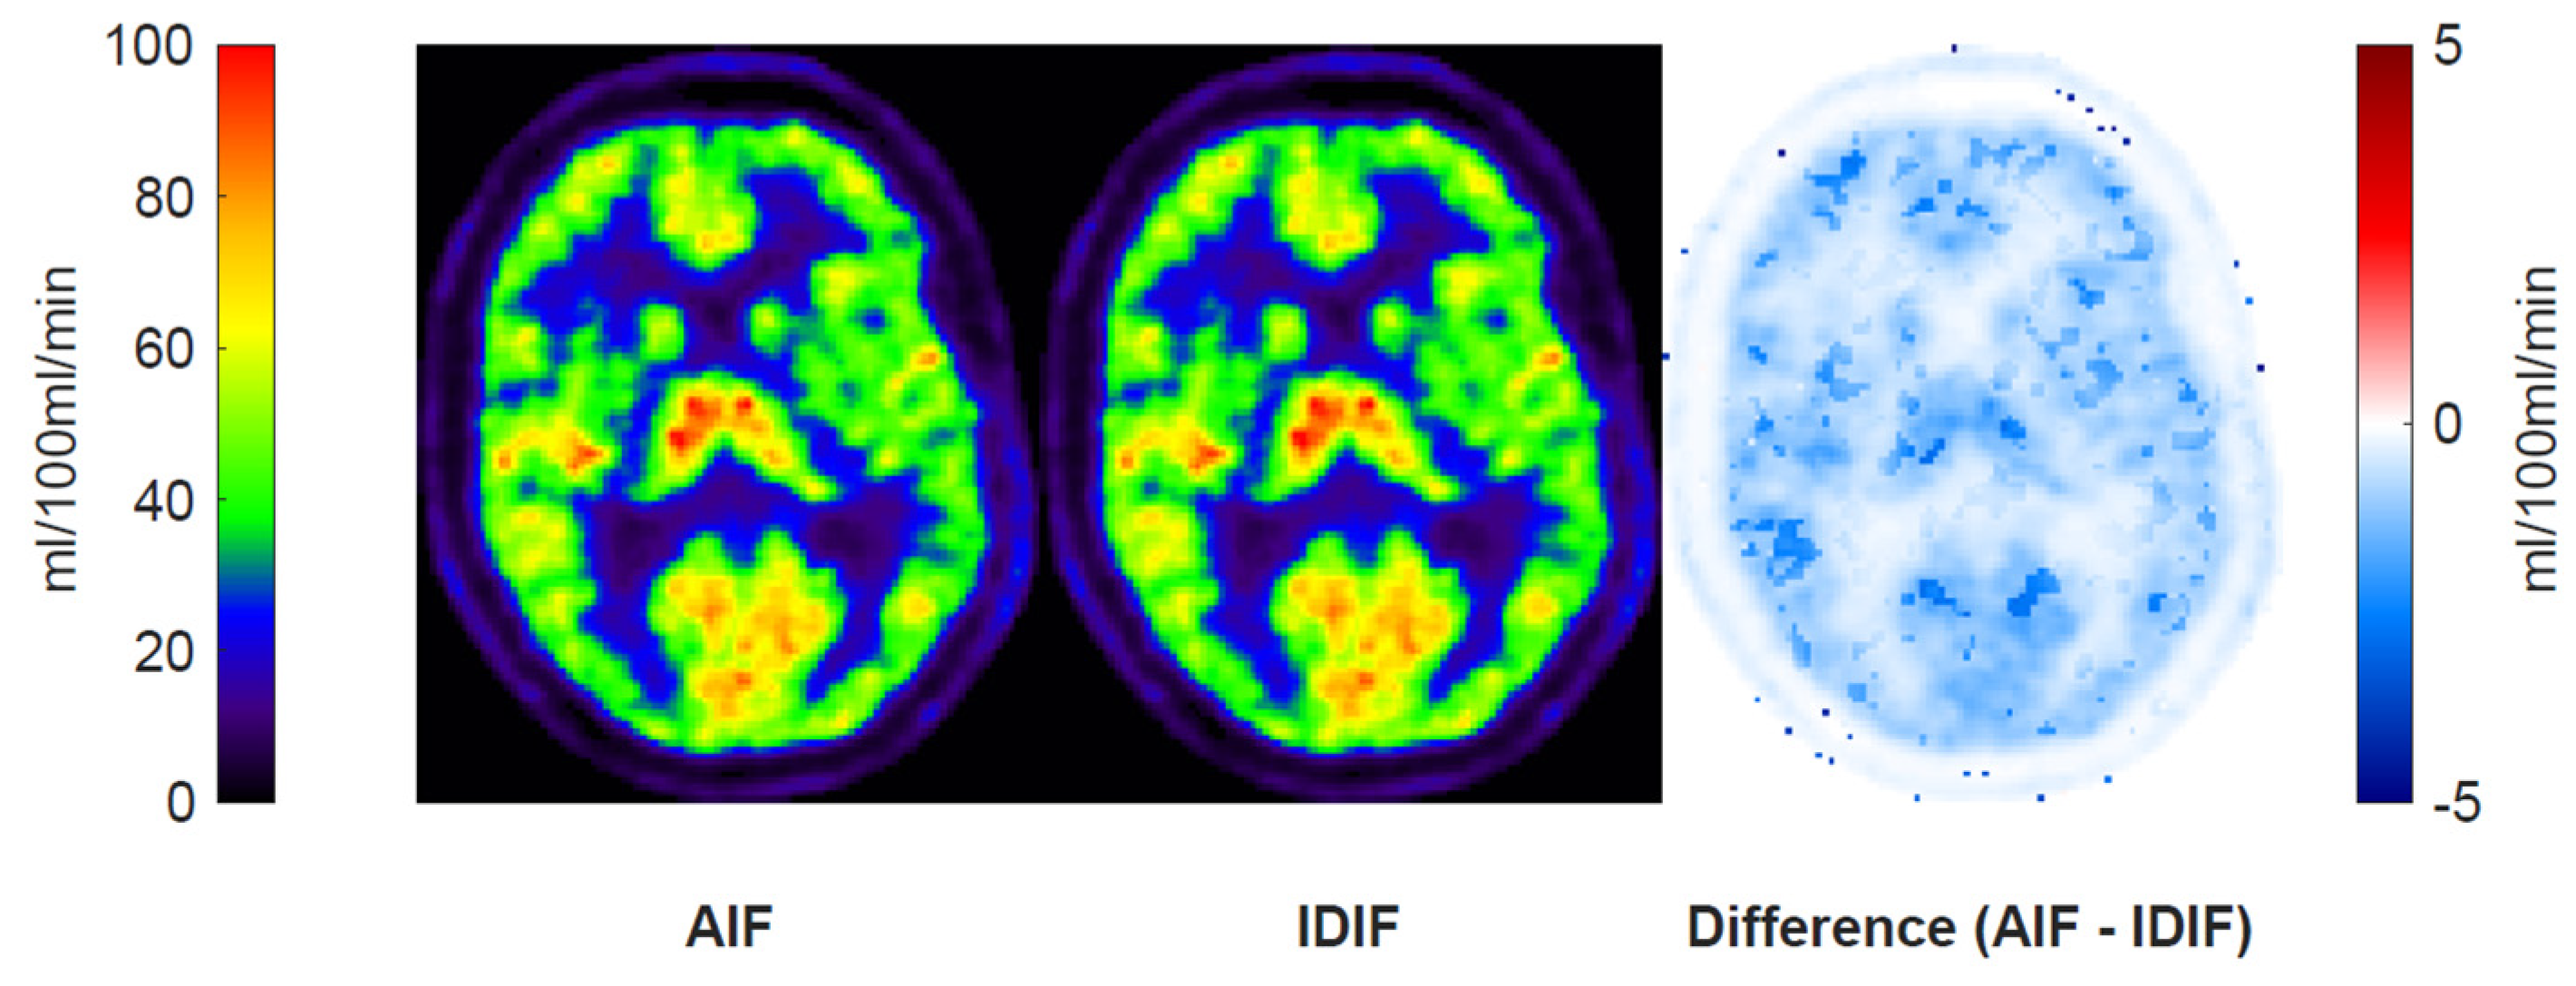

3.1. Blood Input Function Comparisons